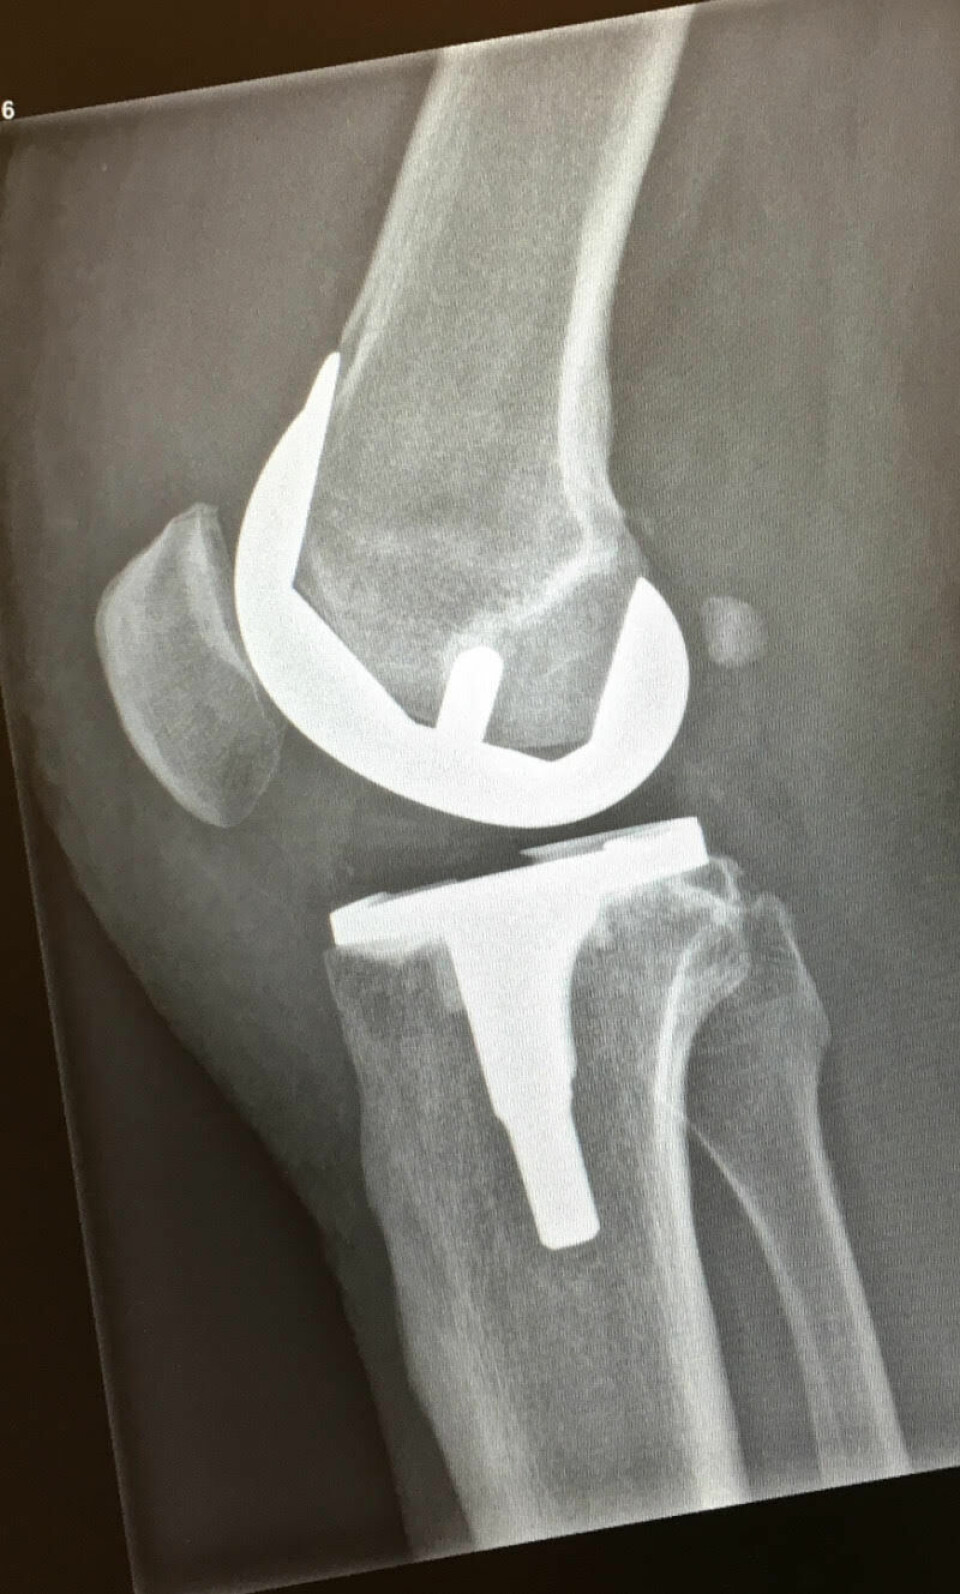

Kneprotese

Lysten til å få orden på bena ble større og større, og mitt første titantilskudd kom da jeg fikk en full protese i høyre kne i 2016. Etter inngrep og opptrening trodde jeg at også løping skulle gå greit, men det gjorde det egentlig ikke i første omgang.

Mentalt ønsket jeg å komme raskt i gang med løpingen, men kroppen brukte lang tid på å tilvenne seg. Resultatet ble mange småskader og avbrekk i treningen til tross for mye styrketrening og fysio. Kneet var – og er fortsatt – litt hovent, men det var ikke det som begrenset treningen.

Hofteprotese

Etter seks år med en del løping og mange vondter samt en ny skavank som stadig ble mye verre, bestemte jeg meg for mitt andre titantilskudd, en protese i venstre hofte (usementert total protese Polar3) med operasjon i februar 2022. Trolig ble belastningen for stor for hoften både før og etter kneoperasjonen.

Min første protese som 50-åring kom i relativt ung alder, men sett i ettertid burde kneoperasjonen vært utført mye tidligere! Livskvaliteten var lenge betydelig redusert for meg som er glad i fysisk aktivitet. Slitasje ved å gå rundt og humpe kan i tillegg ødelegge andre ledd, i mitt tilfelle hoften på motsatt side.

Dette har nok også en sammenheng med at en protese har begrenset levetid og muligens slites raskere av en aktiv person. Dersom innfestningspunktet (benet) blir ødelagt, kan det være komplisert å få festet en ny protese.